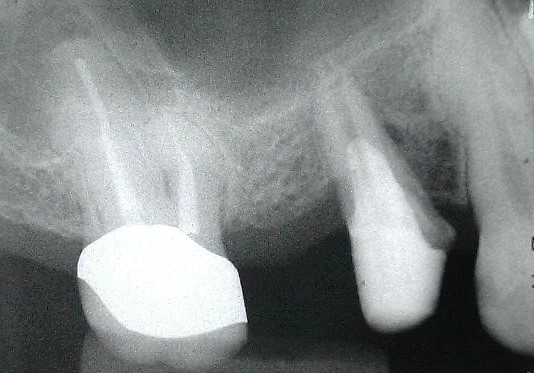

補綴後

治療途中

再植後、4~6か月程経過を見て骨や歯茎の状態が良くなってきたところで被せ物を入れていきます。